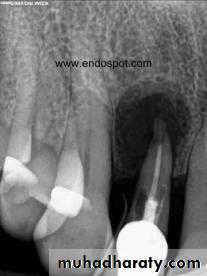

Radiographic features:

Initially, No radiographic change.

With progression, slight widening of PDL, lamina dura may become less defined.Histopathological features:

Most lesions are discovered on routine radiographic examination.A well-defined radiolucency of bone apical to the offending tooth. Loss of the apical lamina dura.

The lesion may be circumscribed or ill defined.

Cyst of long standing may undergo an acute exacerbation which lead to abscess formation.Radiographic Features.

in most cases is identical to periapical granuloma,but, the cyst may be of greater size than the granuloma.Occasionally the apical periodontal cyst exhibits a thin, radiopaque line around the periphery of the radiolucent area, and this indicates a reaction of the bone to the slowly expanding mass.